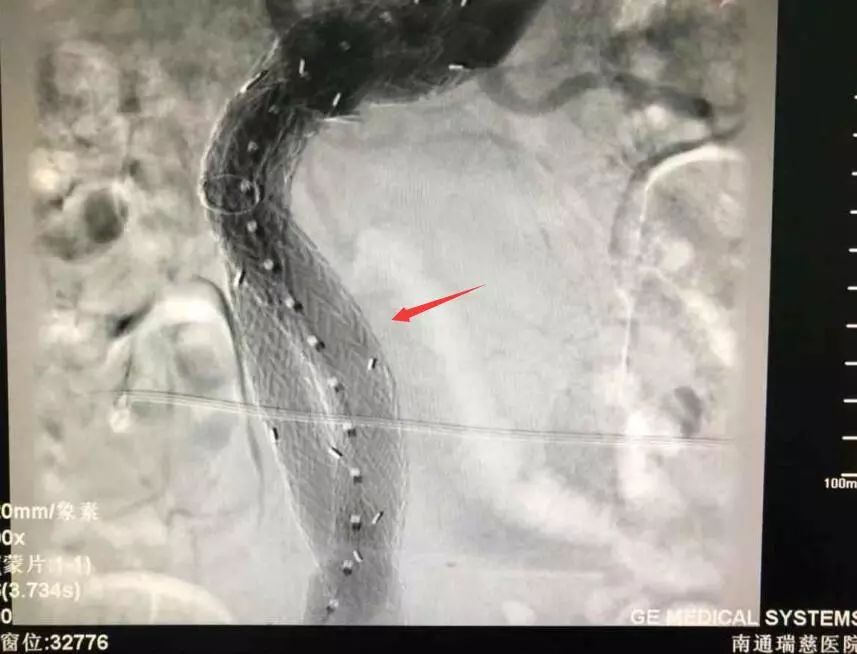

植入支架后動(dòng)脈瘤顯影消失

回憶手術(shù)過(guò)程時(shí),王主任說(shuō),老楊的手術(shù)相對(duì)來(lái)說(shuō)確實(shí)難度較高,由于瘤體大,血液在里面形成渦流,導(dǎo)絲前進(jìn)時(shí)容易彎折,無(wú)論是支架定位還是支架釋放,整個(gè)過(guò)程都十分考驗(yàn)團(tuán)隊(duì)的配合度。常規(guī)手術(shù)一般只用到兩個(gè)支架,老楊的瘤體較長(zhǎng),用上了四根支架才成功完全隔絕動(dòng)脈瘤,杜絕內(nèi)漏的發(fā)生,“就像是在患者的血管內(nèi)建了一個(gè)立交橋,”王主任形容道。